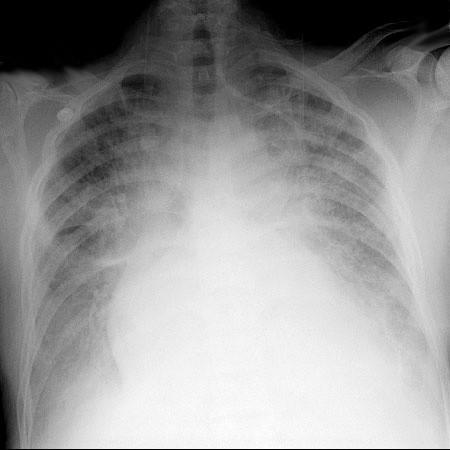

Echokardiografie: LEVÁ KOMORA bez dilatace a hypertrofie, s normální systolickou funkcí a regionální kinetikou kromě D shape, EF LK 55-60%. Diastolická funkce: porucha relaxace LK. PRAVÁ KOMORA FAC PK 18%, TAPSE 13 mm, Vt 9 cm/s, dilatace a hypertrofie PK, těžká prekapilární PH, odhadovaný PASP 90 mmHg, MPAP 55 mmHg, malý perikardiální výpotek

Echokardiografie: LEVÁ KOMORA bez dilatace a hypertrofie, s normální systolickou funkcí a regionální kinetikou kromě D shape, EF LK 55-60%. Diastolická funkce: porucha relaxace LK. PRAVÁ KOMORA FAC PK 19%, TAPSE 17 mm, Vt 9 cm/s, dilatace a hypertrofie PK, těžká prekapilární PH, odhadovaný PASP 130

mmHg, perikardiální výpotek